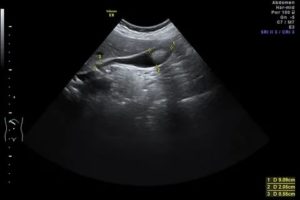

Узи брюшной полости

Узи брюшной полости чаще всего используется для контроля состояния печени, селезенки, желчного пузыря, магистральных сосудов и почек.

Следует обратить внимание на то, что для ультразвукового исследования брюшной полости, а также малого таза наиболее оптимальной считается частота, которая находится в диапазоне 2,5-3,5 МГц.